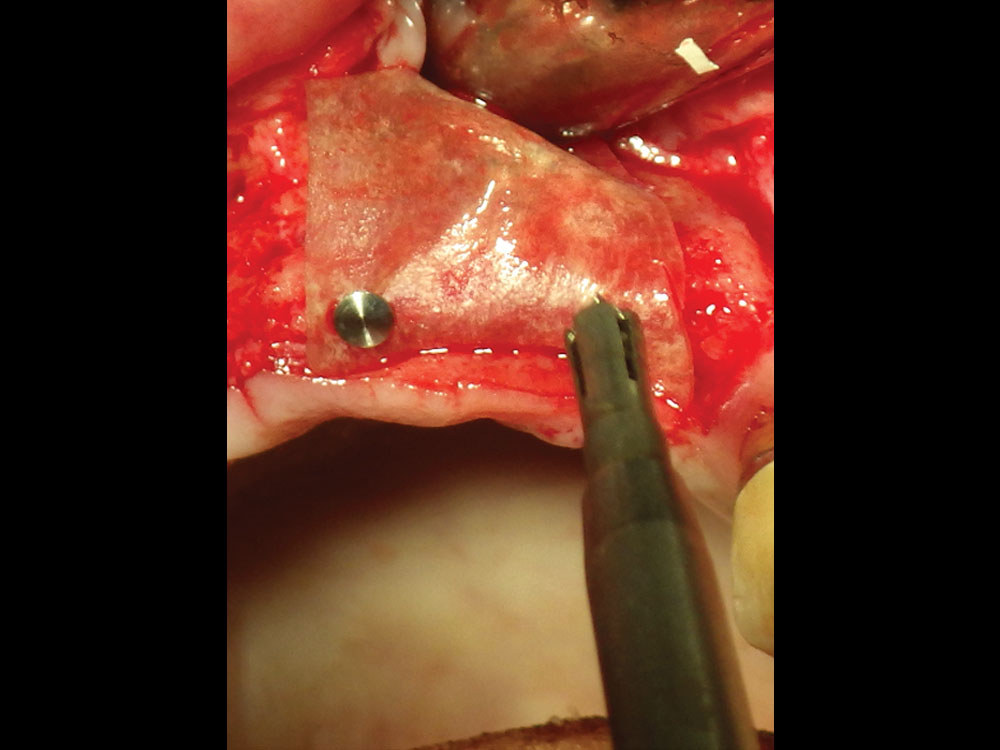

Periosteal release incisions with a No. 15 blade

Broadbased tissue release with Metzenbaum scissors

Figures 8a, 8b: Periosteal release incisions with a No. 15 blade (8a), and broadbased tissue release with Metzenbaum scissors (8b).